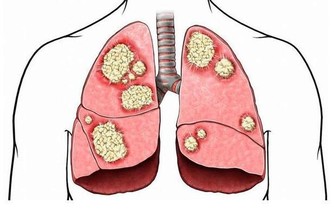

醫生認為,牛奶中的 beta-CM-7 蛋白會造成鼻涕阻塞,尤其是有肺病史的人群。

慢性鼻竇炎患者除了有上述症狀外,還會伴有咳嗽、支氣管炎和哮喘。